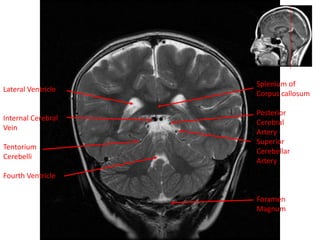

Lateral Ventricle

Splenium of

Corpus callosum

Posterior

Cerebral

Artery

Superior

Cerebellar

Foramen

Magnum

Internal Cerebral

Vein

Tentorium

Cerebelli

Fourth Ventricle

Splenium of Corpus callosum Posterior Cerebral Artery Superior Cerebellar Artery Foramen Magnum LateralVentricle Internal Cerebral Vein Tentorium Cerebelli Fourth Ventricle